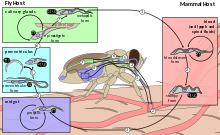

T. brucei completes its life cycle between tsetsefly (of the genus Glossina) and mammalian hosts, including humans, cattle, horses, and wild animals.

In mammalian host

Infection occurs when a vector tsetse fly bites a mammalian host. The fly injects the metacyclic trypomastigotes into the skin tissue. The trypomastigotes enter the lymphatic system and into the bloodstream. The initial trypomastigotes are short and stumpy. Once inside the bloodstream, they grow into long and slender forms. Then, they multiply by binary fission. The daughter cells then become short and stumpy again.[12][13] The long slender forms are able to penetrate the blood vessel endothelium and invade extravascular tissues, including the central nervous system (CNS).[11]

Sometimes, wild animals can be infected by the tsetsefly and they act as reservoirs. In these animals, they do not produce the disease, but the live parasite can be transmitted back to the normal hosts.[12]

In tsetse fly

The short and stumpy trypomastigotes are taken up by tsetse fly during blood meal. The trypomastigotes enter the midgut of the fly where they become procyclic trypomastigotes. These rapidly divide to become epimastigotes. The epimastigotes migrate from the gut via the proventriculus to the salivary glands where they get attached to the salivary gland epithelium. In the salivary glands, some parasites detach and undergo transformation into short and stumpy trypomastigotes. These become the infective metacyclic trypomastigotes. They are injected into the mammalian host along with the saliva on biting. Complete development in the fly takes about 20 days.[12][13]